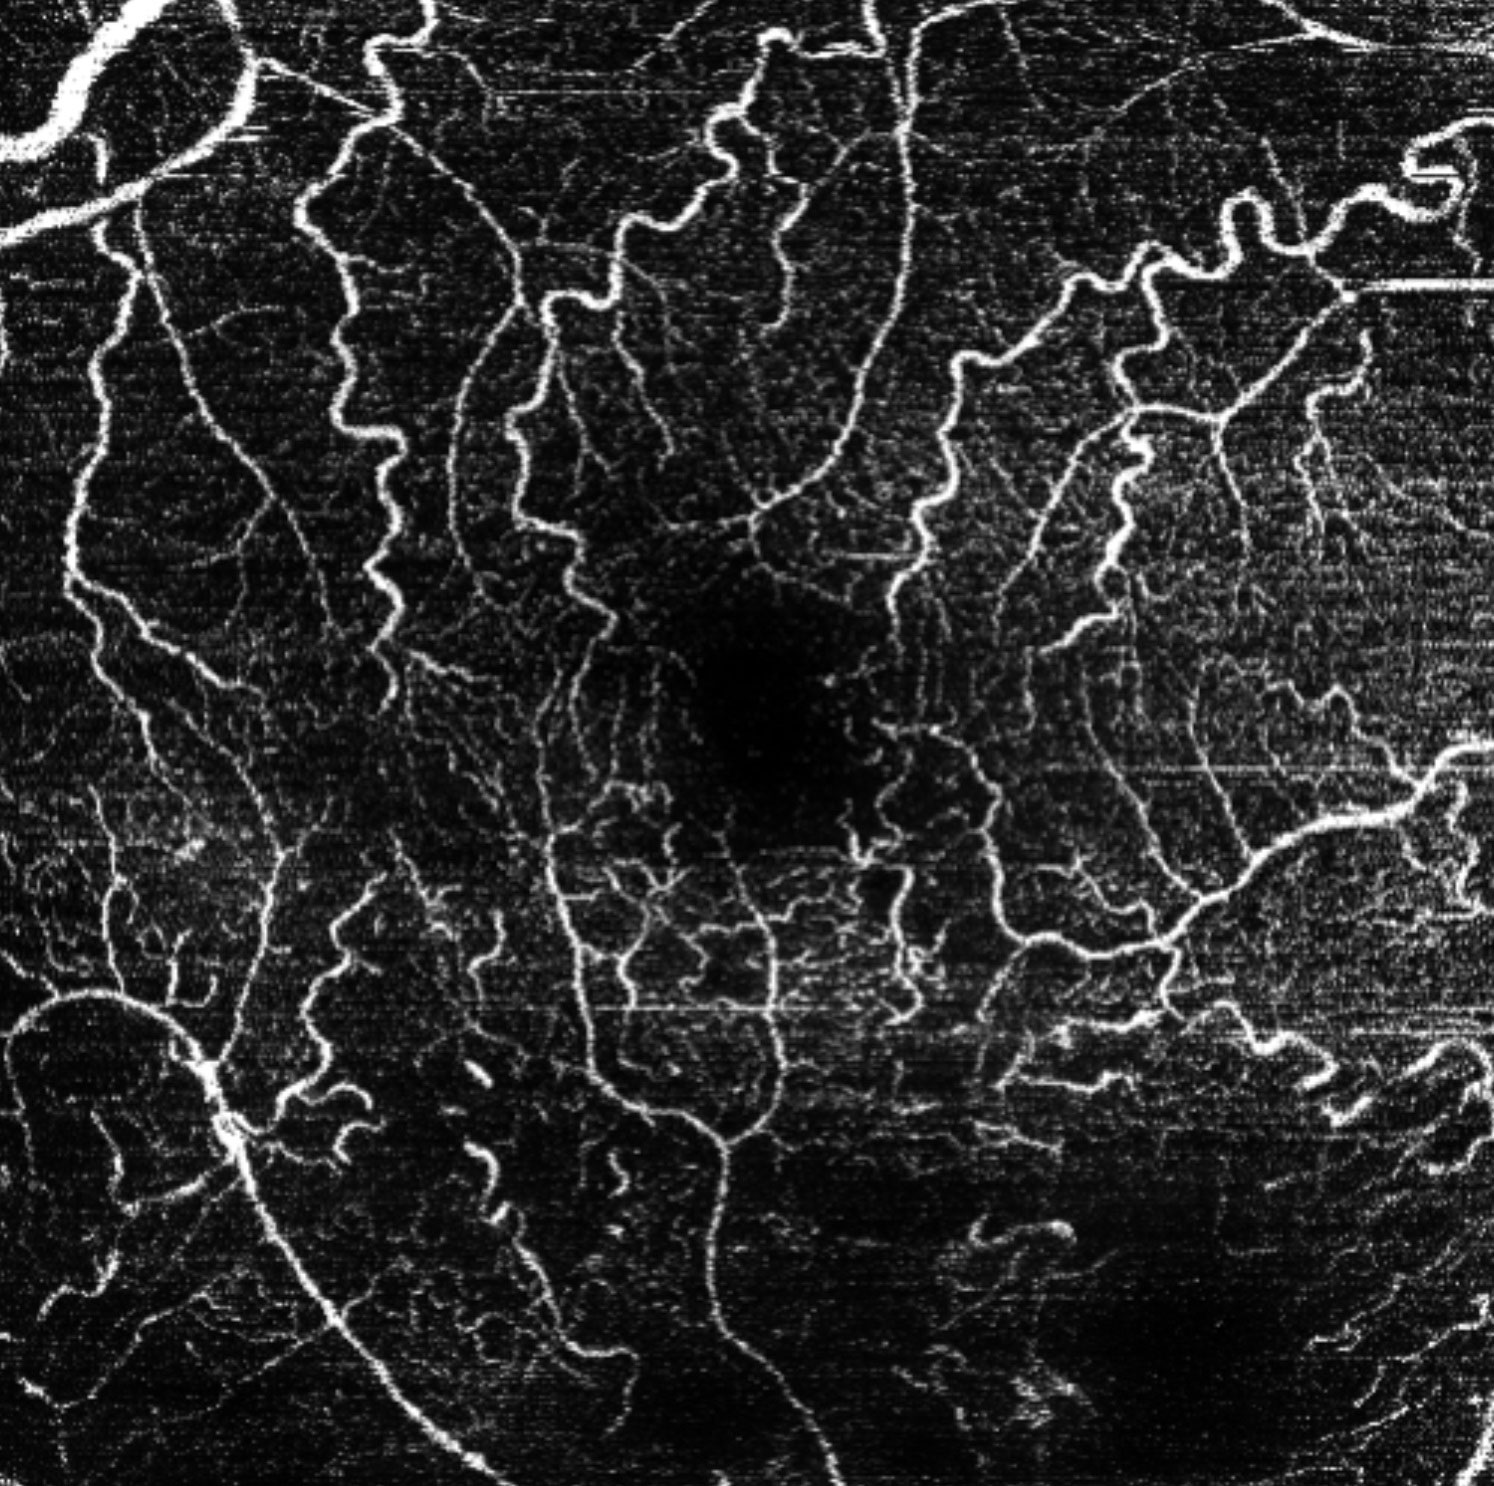

Offering the ideal speed-quality ratio for OCTA, 125 kHz allows you to increase your throughput without any clinically relevant loss in image quality in comparison to the current 85 kHz scan speed. The fast acquisition of images allows for visualization of flow, even in miniscule vessels, while minimizing artefacts, resulting in sharp and detailed images of the capillary network. Additionally, you can decrease chair time when you speed up acquisition with the Glaucoma Module Premium Edition in your glaucoma workflow, if applicable.

125 kHz – A fast scan speed for improved workflow and high OCTA image quality.